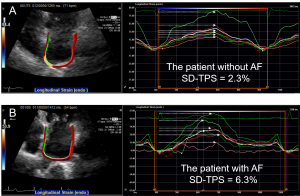

3. Left Atrial Mechanical Dispersion Assessed by Strain Echocardiography as an Independent Predictor of New-onset Atrial Fibrillation: A Case-Control Study

これはDispersion研究の心房版です。画像関連の流行は心室から始まって心房に移っていきますが、これはその典型です(笑)。LV dispersionがVAの予測因子なら、LA dispersionはAFの予測因子になるのではないかという仮説の検討です。LA dispersionとAFの関連性はAF ablation後の再発予測などで検討が始まっておりますが、まだまだ確立されていない分野です。今回の検討ではLA dispersionは左房拡大がない症例でも新規AF発症の予測因子であることが明らかになりました。AHA2018で発表し、現在論文を準備中です。

図3: 洞調律中に評価した心房ストレイン。その後に新規AFを認めた患者(B)の方がストレインのばらつき(SD-TPS: standard deviation of time to peak positive strain)が大きい。